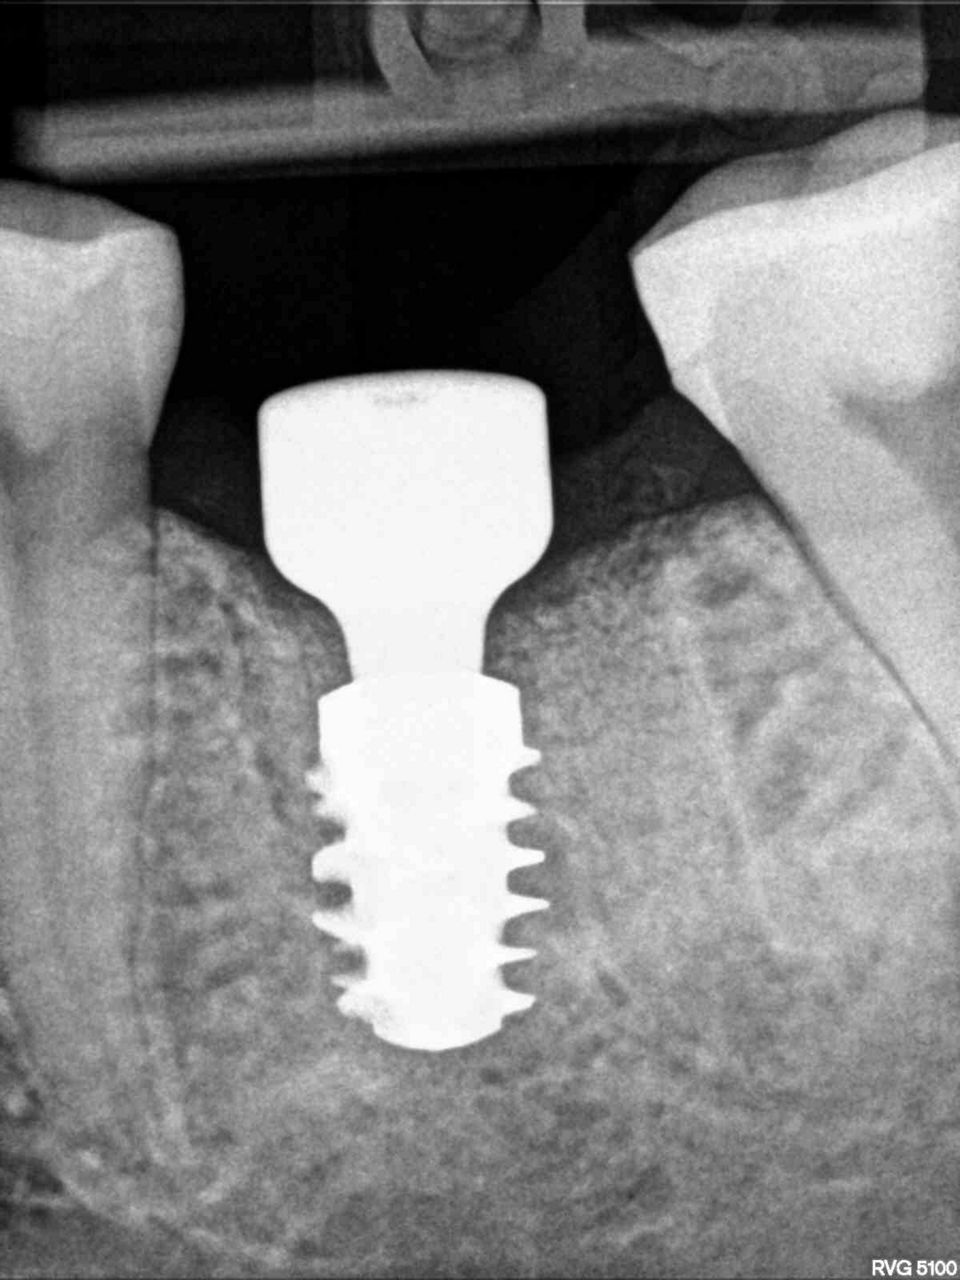

#36 牙的手术过程从局部麻醉和下牙槽神经阻滞开始。通过分割磨牙根实现无翻瓣反射的无创拔牙;从而保留肺泡壁和根间隔膜(图3-4)。仔细清洁牙槽,形成种植体路径并放置Straumann ® BLX 种植体 5.5 x 8 mm (图 5-7)。为了促进非浸没式愈合,将标准愈合基台连接至种植体。骨壁和种植体之间的间隙填充有同种异体骨材料颗粒(maxgraft®,botiss 生物材料,德国)。应用富含血小板的纤维蛋白(PRF)来实现适当的初步愈合。调整软组织边缘并用聚丙烯 6/0 缝合,使愈合基台暴露(图 8-9)。将粘性牙周Reso-Pac ®敷料(来自德国杜伊斯堡的Hager & Werken)放置在治疗区域上以协助愈合过程(图10)。

手术后一周,拆线(图11-12)。在同一次就诊时,拍摄了垂直牙科射线照片(图 13),显示种植体处于正确的修复位置。四个月后,愈合基台被移除。粘膜外观表明植入物周围有稳定且健康的软组织,具有足够的生物宽度和光滑的出现轮廓(图14-15)。取印模,一个月后,将最终的氧化锆陶瓷牙冠拧到种植体上(图 16-18)。